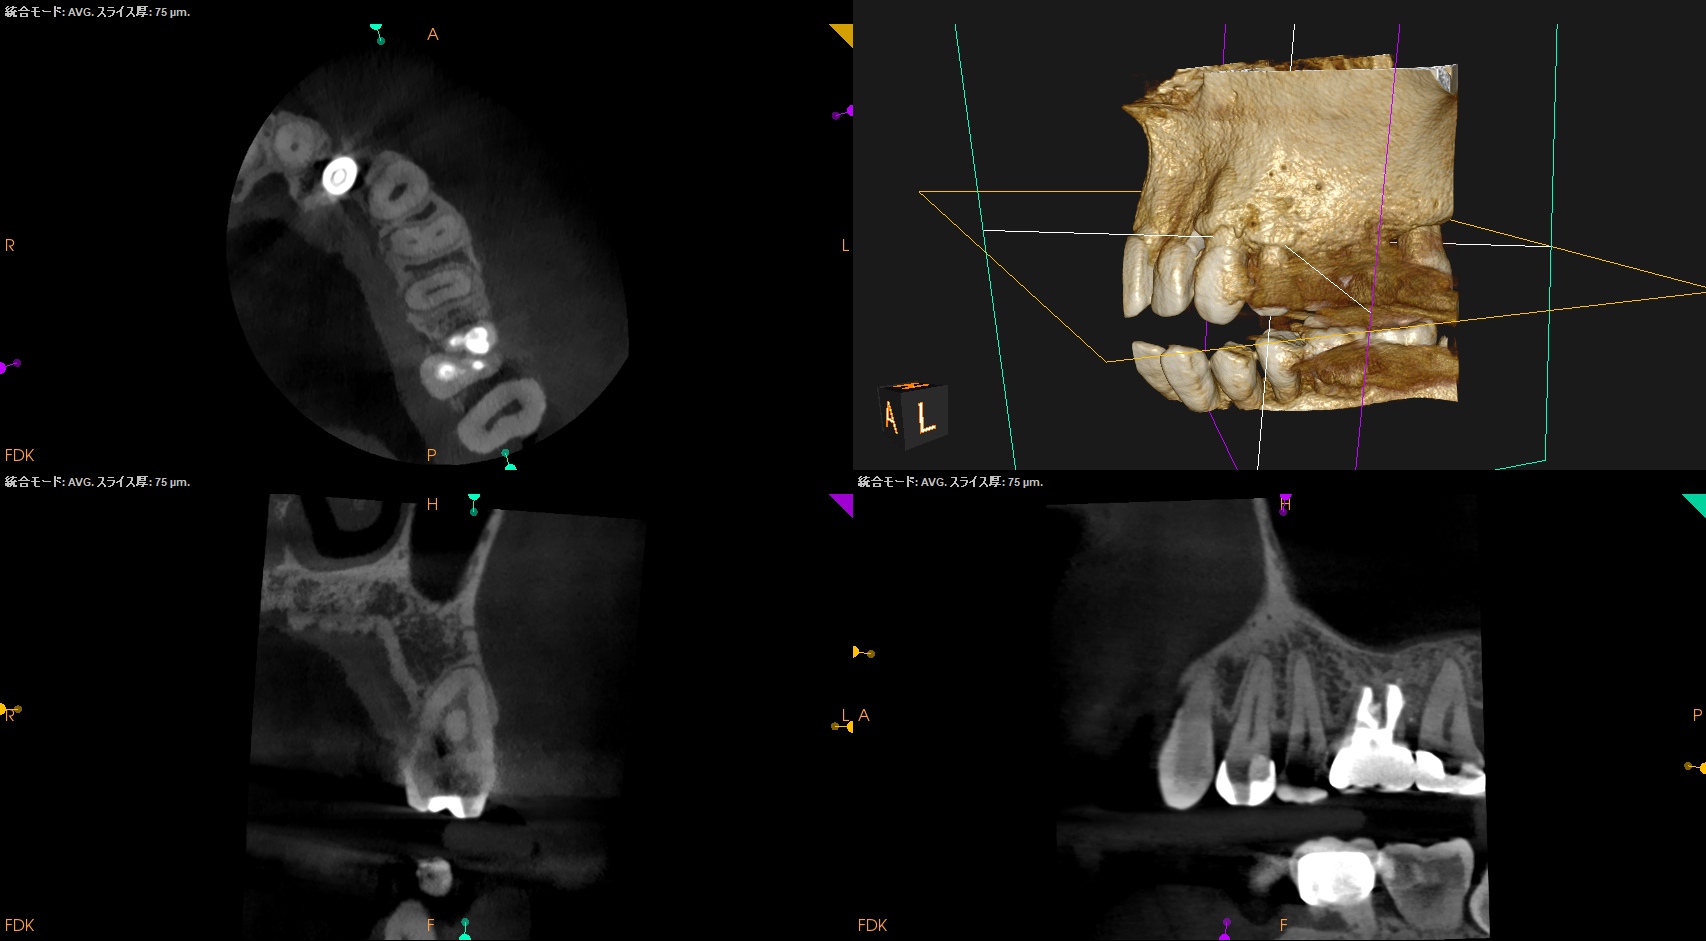

PA(2026.1.6)

Inlay除去後のCR修復は適合がいいとは決していえない感じだ。

2根管性で非機能咬頭のBが直線根管だ。

直覆のような処置がなされた形跡がある。

成人での直覆の成功率は低いことがすでにわかっていることから臨床症状と相まって#12 RCTが主訴の解決に寄与する可能性が高いだろう。

また、治療前のCBCTで2根管性のことから合流部位の確認をいつものように行った。